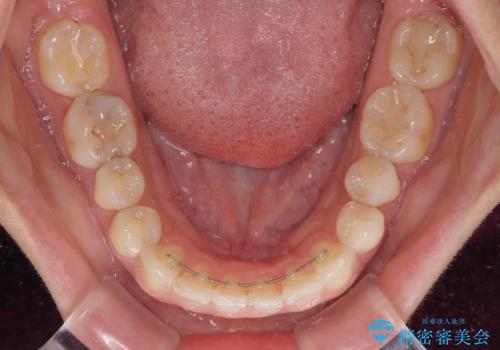

インビザラインにて抜歯矯正を行うと、高頻度で奥歯が咬み合わなくなります。

抜歯スペースが閉じてからも咬みにくさ改善のためマウスピース矯正を継続するため、治療期間は長期化します。